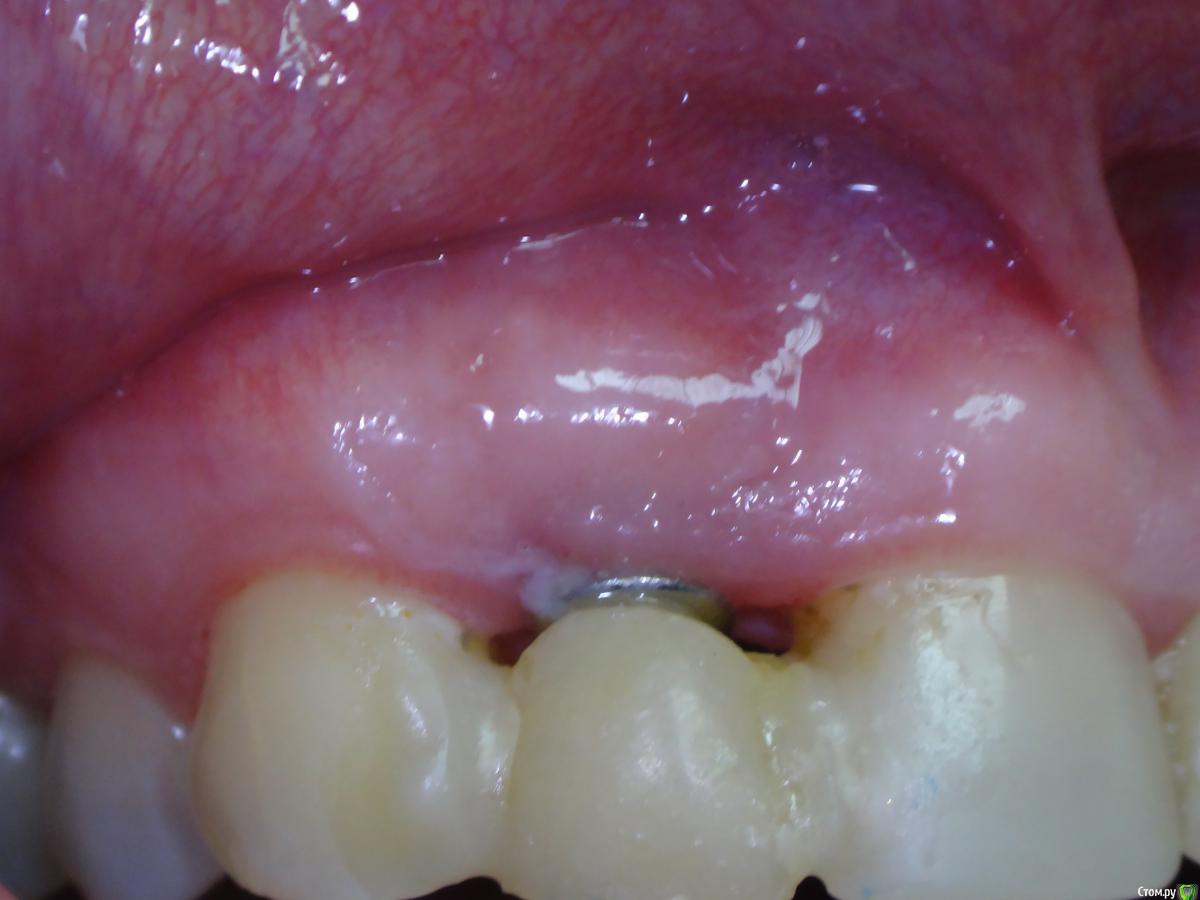

Slaggy Опубликовано 19 июля, 2016 Поделиться Опубликовано 19 июля, 2016 История -Корень 22 с выведением материала и периапикальным процессом - Удаление, кюретаж, обработка лазером, имплант+фдм и домик Нуф-Нуфа приклеенный к 21 и 23.Через 4 месяца выкрутился за формирователь. Куча грануляций, вестибулярное окно на уровне апикальной трети импланта маргинальный край кости сохранен.. Сделано -Кюретаж, Остеон2, пародонкол, ушито. Домик Нуф-Нуфа возведен вновь. По прошествии 2х месяцев -Пациент жалуется на увеличение пространства между понтиком и десной. Периодическое попадание крошек материала в полость рта. Слизистая малинового цвета. Отека нет. "Промывное пространство" увеличилось на 2 мм. В толще слизистой гранулы Остеона. Некоторые совсем у поверхности, можно ковырять зондиком..Боли или неприятных ощущение пациент не испытывает. Убирать все или подождать? Чего ждать от ситуации? Ссылка на комментарий

Slaggy Опубликовано 15 августа, 2016 Автор Поделиться Опубликовано 15 августа, 2016 (изменено) Тут просили картинки-20/05,2016 , 15/08,2016 Графт продолжает всплывать через слизистую, хрустит при пальпации области аугментации Почистил слизистую от графта, дам паузу 2 недели и вычищаю все начисто. Изменено 15 августа, 2016 пользователем Slaggy Ссылка на комментарий